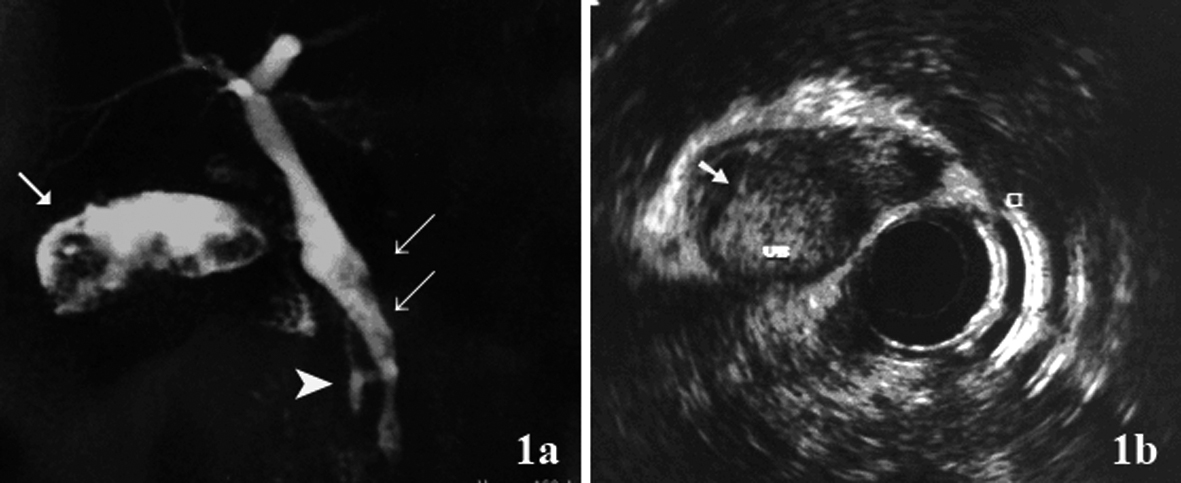

To describe the following case we have written permission of the patient. One female patient, 55-year-old, without biliary disease, was presented with transient icterus and pain and sensitivity on the epigastrium and right upper quadrant. Liver function tests were GGT = 92 IU/L, FA = 172 IU/L, TGO = 23 IU/L, TGP = 29 IU/L, BT = 0.5 mg/dL. In addition, tumor markers, including carbohydrate antigen 19-9 (CA 19.9), carcinoembryonic antigen (CEA) and Alfafetoprotein were within normal ranges. Magnetic resonance cholangiopancreatography (MRCP) showed bile duct dilatation and filling defect and pancreaticobiliary maljunction (Fig. 1a). Endoscopic ultrasound revealed dilated extrahepatic bile duct (CBD) with hyperechoic foci with no acoustic shadowing within, and a hyperechoic frond-like mass was noted within the infundibulum of gallbladder (Fig. 1b). Open cholecystectomy was performed and frozen section diagnosed gallbladder adenocarcinoma (Fig. 2a). The operation was completed with liver resection including segments 4b and 5, partial resection of the common bile duct and lymphadenectomy of the hepatic pedicle. Microscopic findings were gallbladder papillary carcinoma on the background of tubulopapillary adenoma (Fig. 2b, c) and carcinoma in situ in hepatic duct of segment 5 (Fig. 2d).

![]() Click for large image | Figure 1. (a) Magnetic resonance cholangiopancreatography (MRCP) showed hyperdense structure within the gallbladder infundibulum, which were suggestive of tumor (arrow), bile duct dilatation and filling defect (double arrow) and pancreaticobiliary maljunction(arrow head); (b) Endoscopic ultrasound showed hyperechoic frond-like mass within the gallbladder (arrow). |